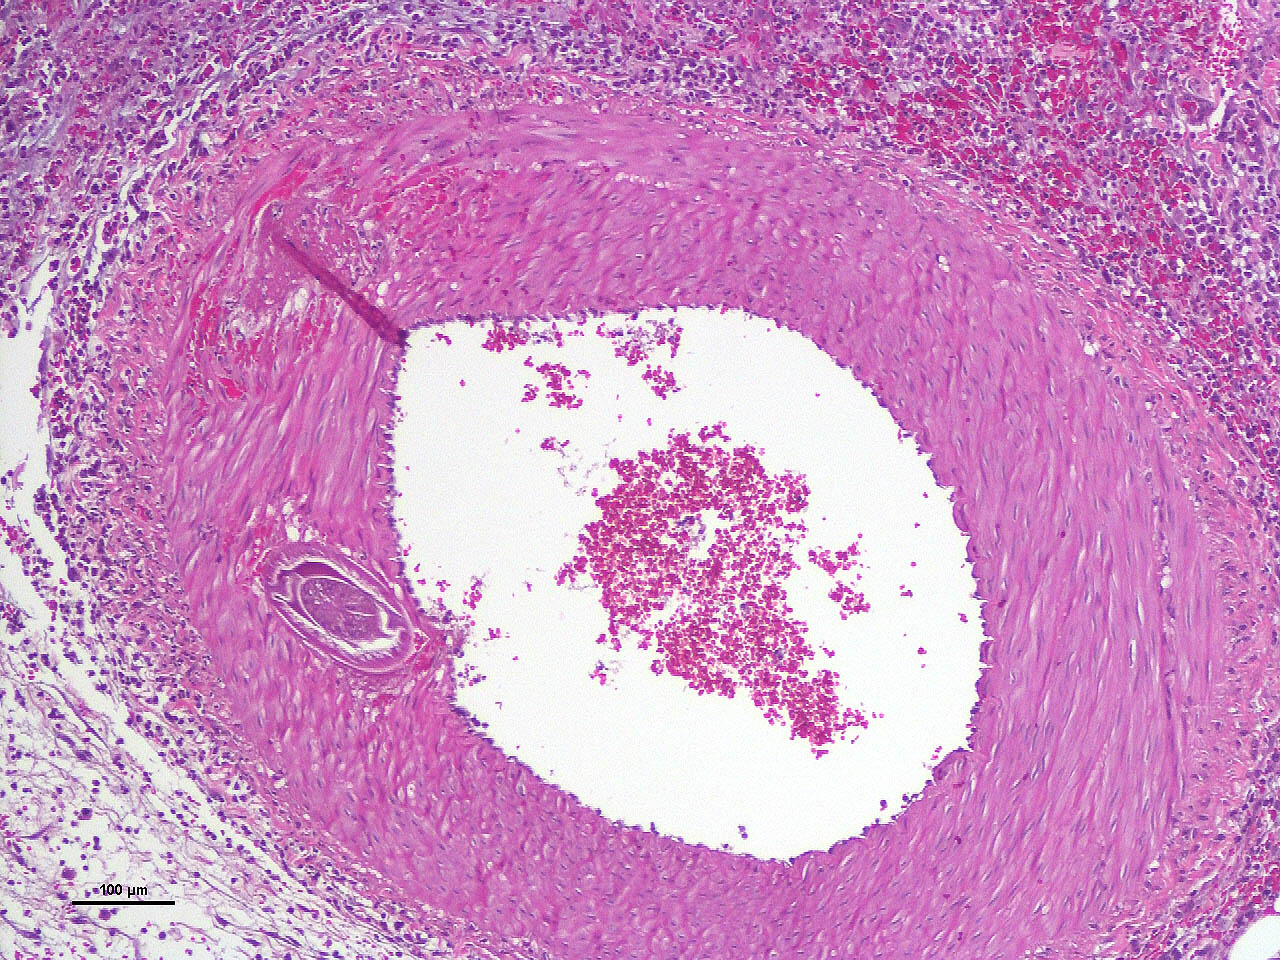

Within the media of medium to small sized arteries there were sections (not present in all slides due to the small size of the parasite – but see photomicrographs) of a nematode larva, approximately 100-200 µm in diameter with lateral allae and central digestive tract. These features are consistent with a spirurid of which Spirocerca is the most likely in our region. Foci of necrosis with hemorrhage were observed in the media of some arteries, where no larvae were identified.

Acute transmural necrotizing eosinophilic enteritis and eosinophilic peritonitis with arterial mesenteric thrombi and rare intralesional nematode larvae (spirurid)Contributor's Comment:

Aortic lesions associated with Spirocerca include intimal and medial hemorrhage and necrosis with eosinophilic inflammation, thrombus formation and rarely rupture of the aortic wall.1,2,7

- Mesentery: Arteritis and periarteritis, necrotizing and eosinophilic, chronic, multifocal, severe, with arterial thrombi and rare larval spirurids.

The JPC’s own MAJ Katie Scott moderated Conference 6 and took participants on a journey of cases from around the world; each one was from somewhere outside of the continental U.S., highlighting the truly global nature of the WSC and the importance of international contributions to pathology education. This first case provided an excellent opportunity to review of the pathogenesis and life cycle of Spirocerca lupi, both of which are well-covered in the contributor’s comment. Additionally, the lesions of spirocercosis that are considered pathognomonic in the dog were covered and include aortic scarring with aneurysms, thoracic spondylitis, and caudal esophageal nodules. Special attention was paid to the chronic arterial thrombi present in numerous arteries in this case, which are a classic part of the pathogenesis of this parasite due to its arterial migratory routes and chronic intimal irritation. Participants were also reminded of the importance of specifying what type of vessels (arteries, arterioles, veins, lymphatics, etc.) are affected when giving a description, as this can provide important clues towards pathogenesis of some diseases that may preferentially affect a specific vessel type.Spirocerca lupi is one of a handful of helminths that are classified as Group I carcinogens by the International Agency for Research on Cancer (IARC) due to the well-documented malignant transformation of S. lupi esophageal nodules into esophageal fibrosarcomas or osteosarcomas in up to 25% of infected dogs.6 Less commonly, chondrosarcomas or undifferentiated pleomorphic sarcomas can also be seen.6 Metastasis to multiple locations throughout the body, including the lungs, kidneys, stomach, spleen, heart, and tongue, occurs frequently.6,7 Significantly higher levels of interleukin-8 (IL-8) have been documented in dogs with malignant esophageal nodules.4 IL-8 is released by activated fibroblasts in pre-neoplastic nodules and is chemotactic for neutrophils. IL-8 is also involved in the tumor progression of human herpesvirus-4 (Epstein–Barr virus)-induced carcinomas.4